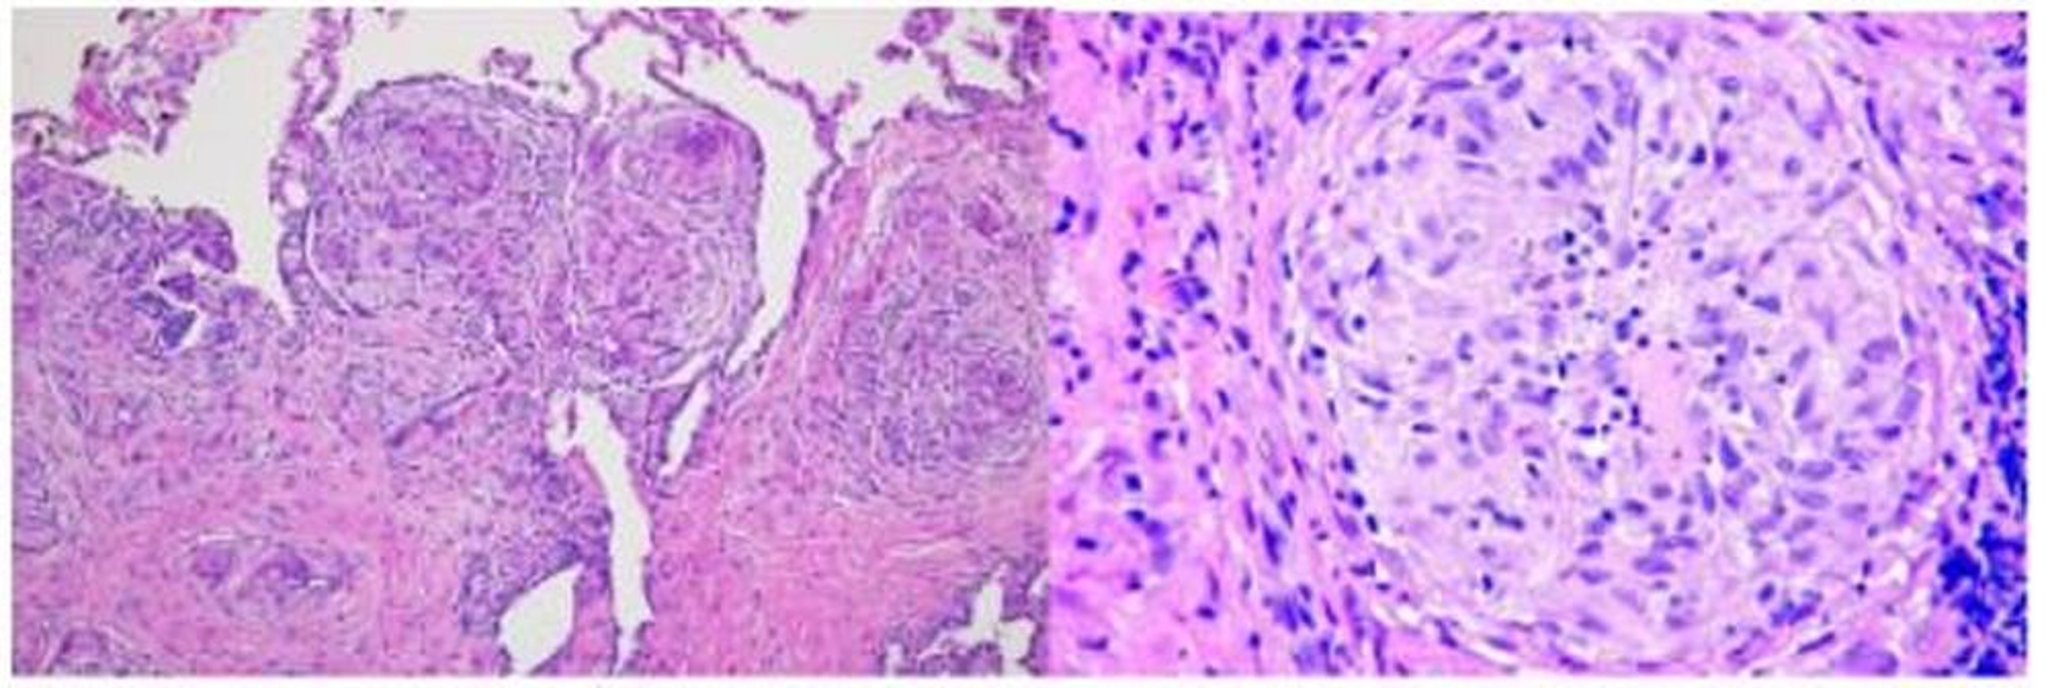

Саркоїдоз (гістопатологія)

In this image, a lung biopsy of a patient with sarcoidosis shows granulomas along the bronchovascular bundle (hematoxylin and eosin stain, low magnification; left) and sarcoid granuloma with multinucleated giant cells in center of granulomas (high magnification; right).

Image courtesy of Birendra P. Sah, MD, FCCP.